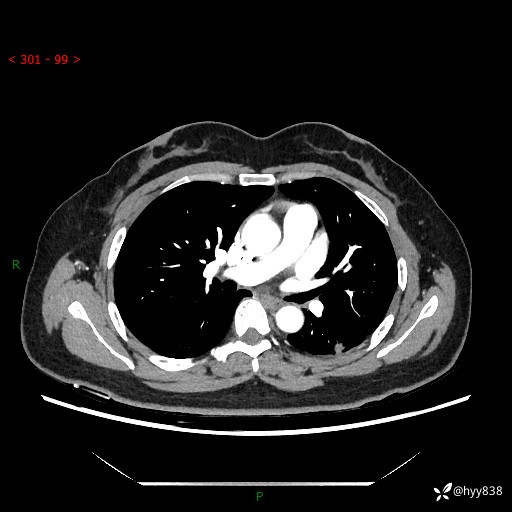

胸部CT复查+增强(2024.6)